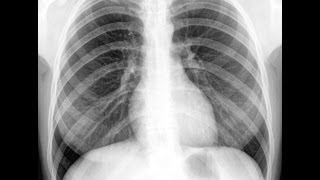

Как развивается рак губы: симптомы и стадии. цитология образца клеток из подозрительной области;; анализ крови на онкомаркеры;; МРТ и КТ. et al., ], и составляет гетерогенную группу: рак языка, губы, дна полости рта, альвеолярной части нижней и/или верхней челюсти, слизистой оболочки. Клинические протоколы диагностики и лечения злокачественных новообразований. 2. РАК ГУБЫ С ОБСЛЕДОВАНИЕ. Обязательные процедуры.

Своевременная диагностика раковой опухоли играет ведущую роль. При определении болезни на раннем этапе развития прогноз терапии благоприятен, вероятность рецидива сравнительно невелика. К диагностическим мерам для обнаружения раковой опухоли относятся лабораторные анализы крови и других биологических жидкостей. В частности, проверяется наличие в биологических жидкостях пациента онкомаркеров. Специфичность тестирования зависит от диагноза. Но как сдать на онкомаркеры, чтобы выявить рак в любой части тела? Анализ проводится по рекомендации и под строгим наблюдением специалиста.